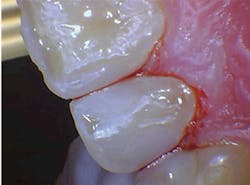

The removal of dental hard tissue is accomplished by what is known as thermomechanical photon-induced water-mediated ablation, which is a process in which the micro-explosive force of photons on water droplets results in the selective removal of carious dentin (figures 2a–2d). The laser energy seeks out tissue with higher water content, such as a carious lesion, and evaporates it without contact, vibration, or the introduction of microfractures, leaving the surrounding healthy enamel and dentin intact.

Figures 2a–2d: A Class II posterior cavity preparation